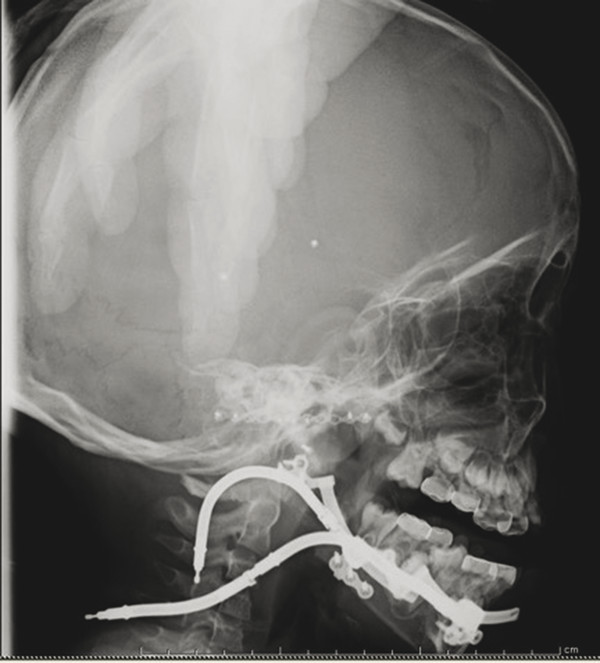

To achieve these goals, a number of different devices have been used throughout the years (Table 10‑3). Initially, external distractor devices utilized transcutaneous pins to fixate either side of the osteotomy site with external distraction arms to exact the lengthening vector (Fig. 10‑2). These devices, with their active parts exposed and available for manipulation, allow for alteration of the distraction vector during the active distraction period. The obvious downsides of these devices include significant bulk and unsightly pin tracks in the skin. Since then, internal devices have been developed. These are placed directly on the bone under the skin and soft tissue; however, periosteum is ideally left intact on at least one side of the osteotomy site to guide the formation of the bony callus. Internal devices also include a distraction arm, which comes through the skin, usually at some length away from the device to discourage infection (Fig. 10‑3). This arm is manipulated to activate distraction of the device. Internal devices can be concealed in a more aesthetic fashion and can be more tolerable to patients and their families, with fewer external components to dislodge. This may permit for longer consolidation periods. However, these can be difficult to securely fixate in very young bone, they must be removed at a second operation, and the vector of internal devices cannot be manipulated during the distraction period.